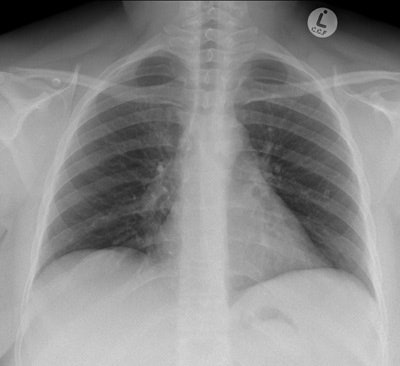

The postoperative radiograph showed no residual fragments.